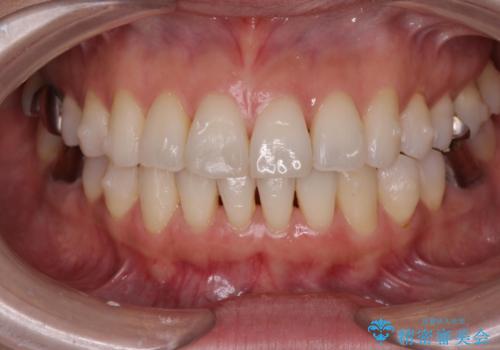

抜歯をせず前歯の角度を改善するマウスピース矯正治療

- 突き出た前歯の角度を改善したい、と矯正治療を希望され来院されました。

抜歯を行いワイヤー矯正で2-3年程度の時間をかけて、しっかり前歯を後方に移動させるか、

抜歯を行わずにIPR(歯の間に空隙を設ける)で可及的に角度の改善を行うか、

2通りの治療方針をご提案しました。

治療期間が約半年で行うことができ、歯を抜かずにマウスピース矯正で可及的に前歯の角度を改善する治療方針を

奥歯の状態等も鑑みて選択されました。

約半年で大きく前歯の角度を改善することができ、抜歯を行わない矯正治療の結果に大変喜んでいただくことができました。